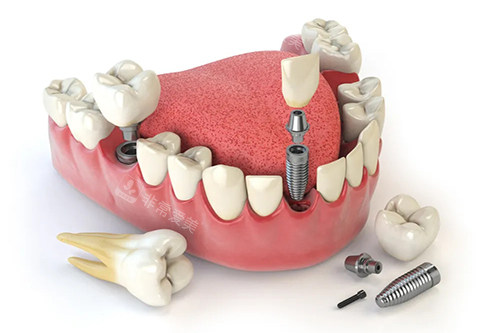

在种植手术中,新型的种植导航系统可以精细引导种植体的植入位置,提高种植的成功概率。